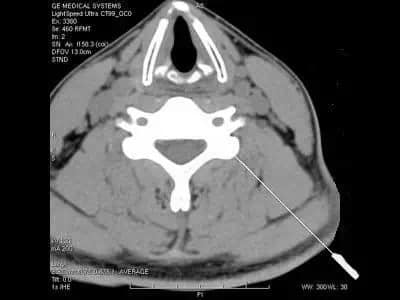

🏮脊髓壓迫病理:

中央後突的髓核、椎體後緣骨刺、黃韌帶增生肥厚、後縱韌帶鈣化等原因使脊髓受到壓迫。